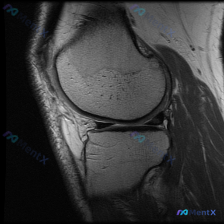

刚整理完这份膝关节MRI的读片思路,这个病例其实挺有代表性,很容易犯锚定错误,分享给大家一起看看。 病例基本影像信息 本次提供的是膝关节MRI矢状位T2加权图像,具体影像学发现如下: 1. 骨骼结构:股骨远端髁前部及滑车无明显骨折,胫骨平台关节面完整无塌陷,髌骨结构未见明显异常;股骨远端周围皮下软组...

最近看到一份膝关节MRI读片需求,初始焦点指向「软骨异常」,整理了完整的分析思路分享给大家。 基本影像信息 这是一张膝关节MRI矢状位脂肪抑制序列(FS-T2/PD-FS)图像,信噪比、对比度良好,无明显运动伪影,定位为:右侧是前(髌骨侧),左侧是后(腘窝侧)。该序列液体呈高信号,骨髓脂肪信号被抑制...

分享一份膝关节MRI读片病例,问题是观察到软骨异常,整理一下完整的读片和分析思路给大家参考。 一、基本影像信息 这是一份膝关节MRI矢状位T1加权图像,我们先整理所有客观观察: 1. 骨骼与骨髓:股骨远端、胫骨近端、髌骨骨皮质完整,无骨质破坏断裂;骨髓信号大致均匀,无局灶性异常低信号,不支持骨髓水肿...